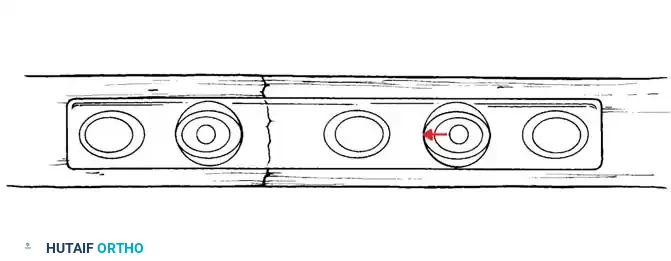

Surgical Warning: A simple wire loop is biomechanically inferior to a figure-of-eight loop. If a simple loop is used—especially if its axis lies anterior to the mid-axis of the olecranon—the pull of the triceps will cause the fragments to separate posteriorly, leading to articular step-off and limited extension.

Fig. 54-53 A and B, Simple loop is not as satisfactory as figure-of-eight loop for fixing fracture of olecranon. C, Simple loop is insufficient when its long axis is in or anterior to long axis of olecranon.